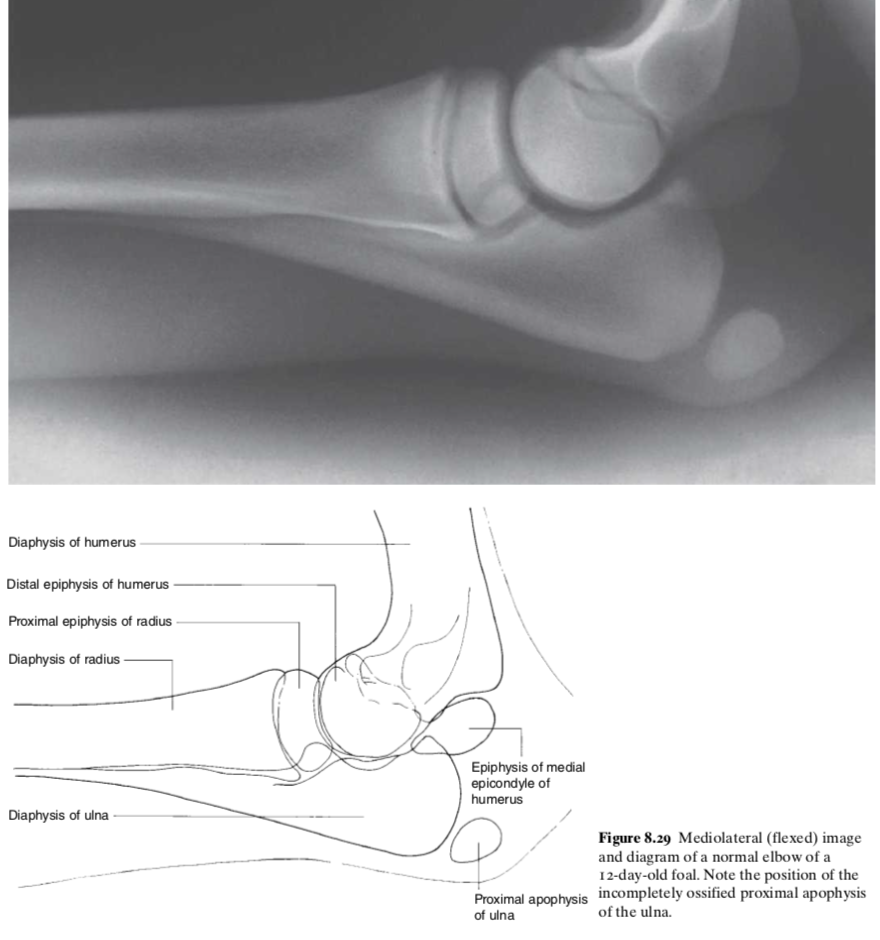

4 physes close to the elbow